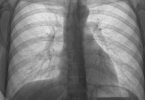

白肺治疗能恢复,但恢复情况取决于病因、严重程度及治疗时机。白肺通常指肺部影像学检查中呈现大片白色区域,常见于重症肺炎、急性呼吸窘迫综合征等疾病。早期诊断和规范治疗是恢复的关键。1、白肺的常见病因包括感 ...

白肺的症状包括呼吸困难、咳嗽、发热和血氧饱和度下降,通过积极治疗可以改善病情。治疗方法包括药物治疗、氧疗和机械通气等。1、白肺的症状表现呼吸困难是白肺的典型症状,患者常感到气短,尤其是在活动后情况加重 ...

白肺症状老人治疗效果好的关键在于及时就医、综合治疗以及良好的护理支持。白肺通常由肺部感染、炎症或其他严重疾病引起,老年人因免疫力较低,易发展为重症,需尽早干预。1、及时就医。白肺是一种严重的肺部疾病, ...

白肺症状的治疗效果和生存期取决于病因、病情严重程度及治疗时机。早期发现并积极治疗,部分患者可以治愈,生存期也能有效延长。治疗方式包括药物、氧疗、机械通气等,医生会根据具体情况制定方案。1、病因与病情分 ...

新生儿白肺治愈后是否会有后遗症取决于病情的严重程度和治疗是否及时。大多数情况下,经过规范治疗后不会留下明显后遗症,但部分重症患儿可能出现长期呼吸功能异常或发育迟缓。1、新生儿白肺的原因新生儿白肺主要是 ...